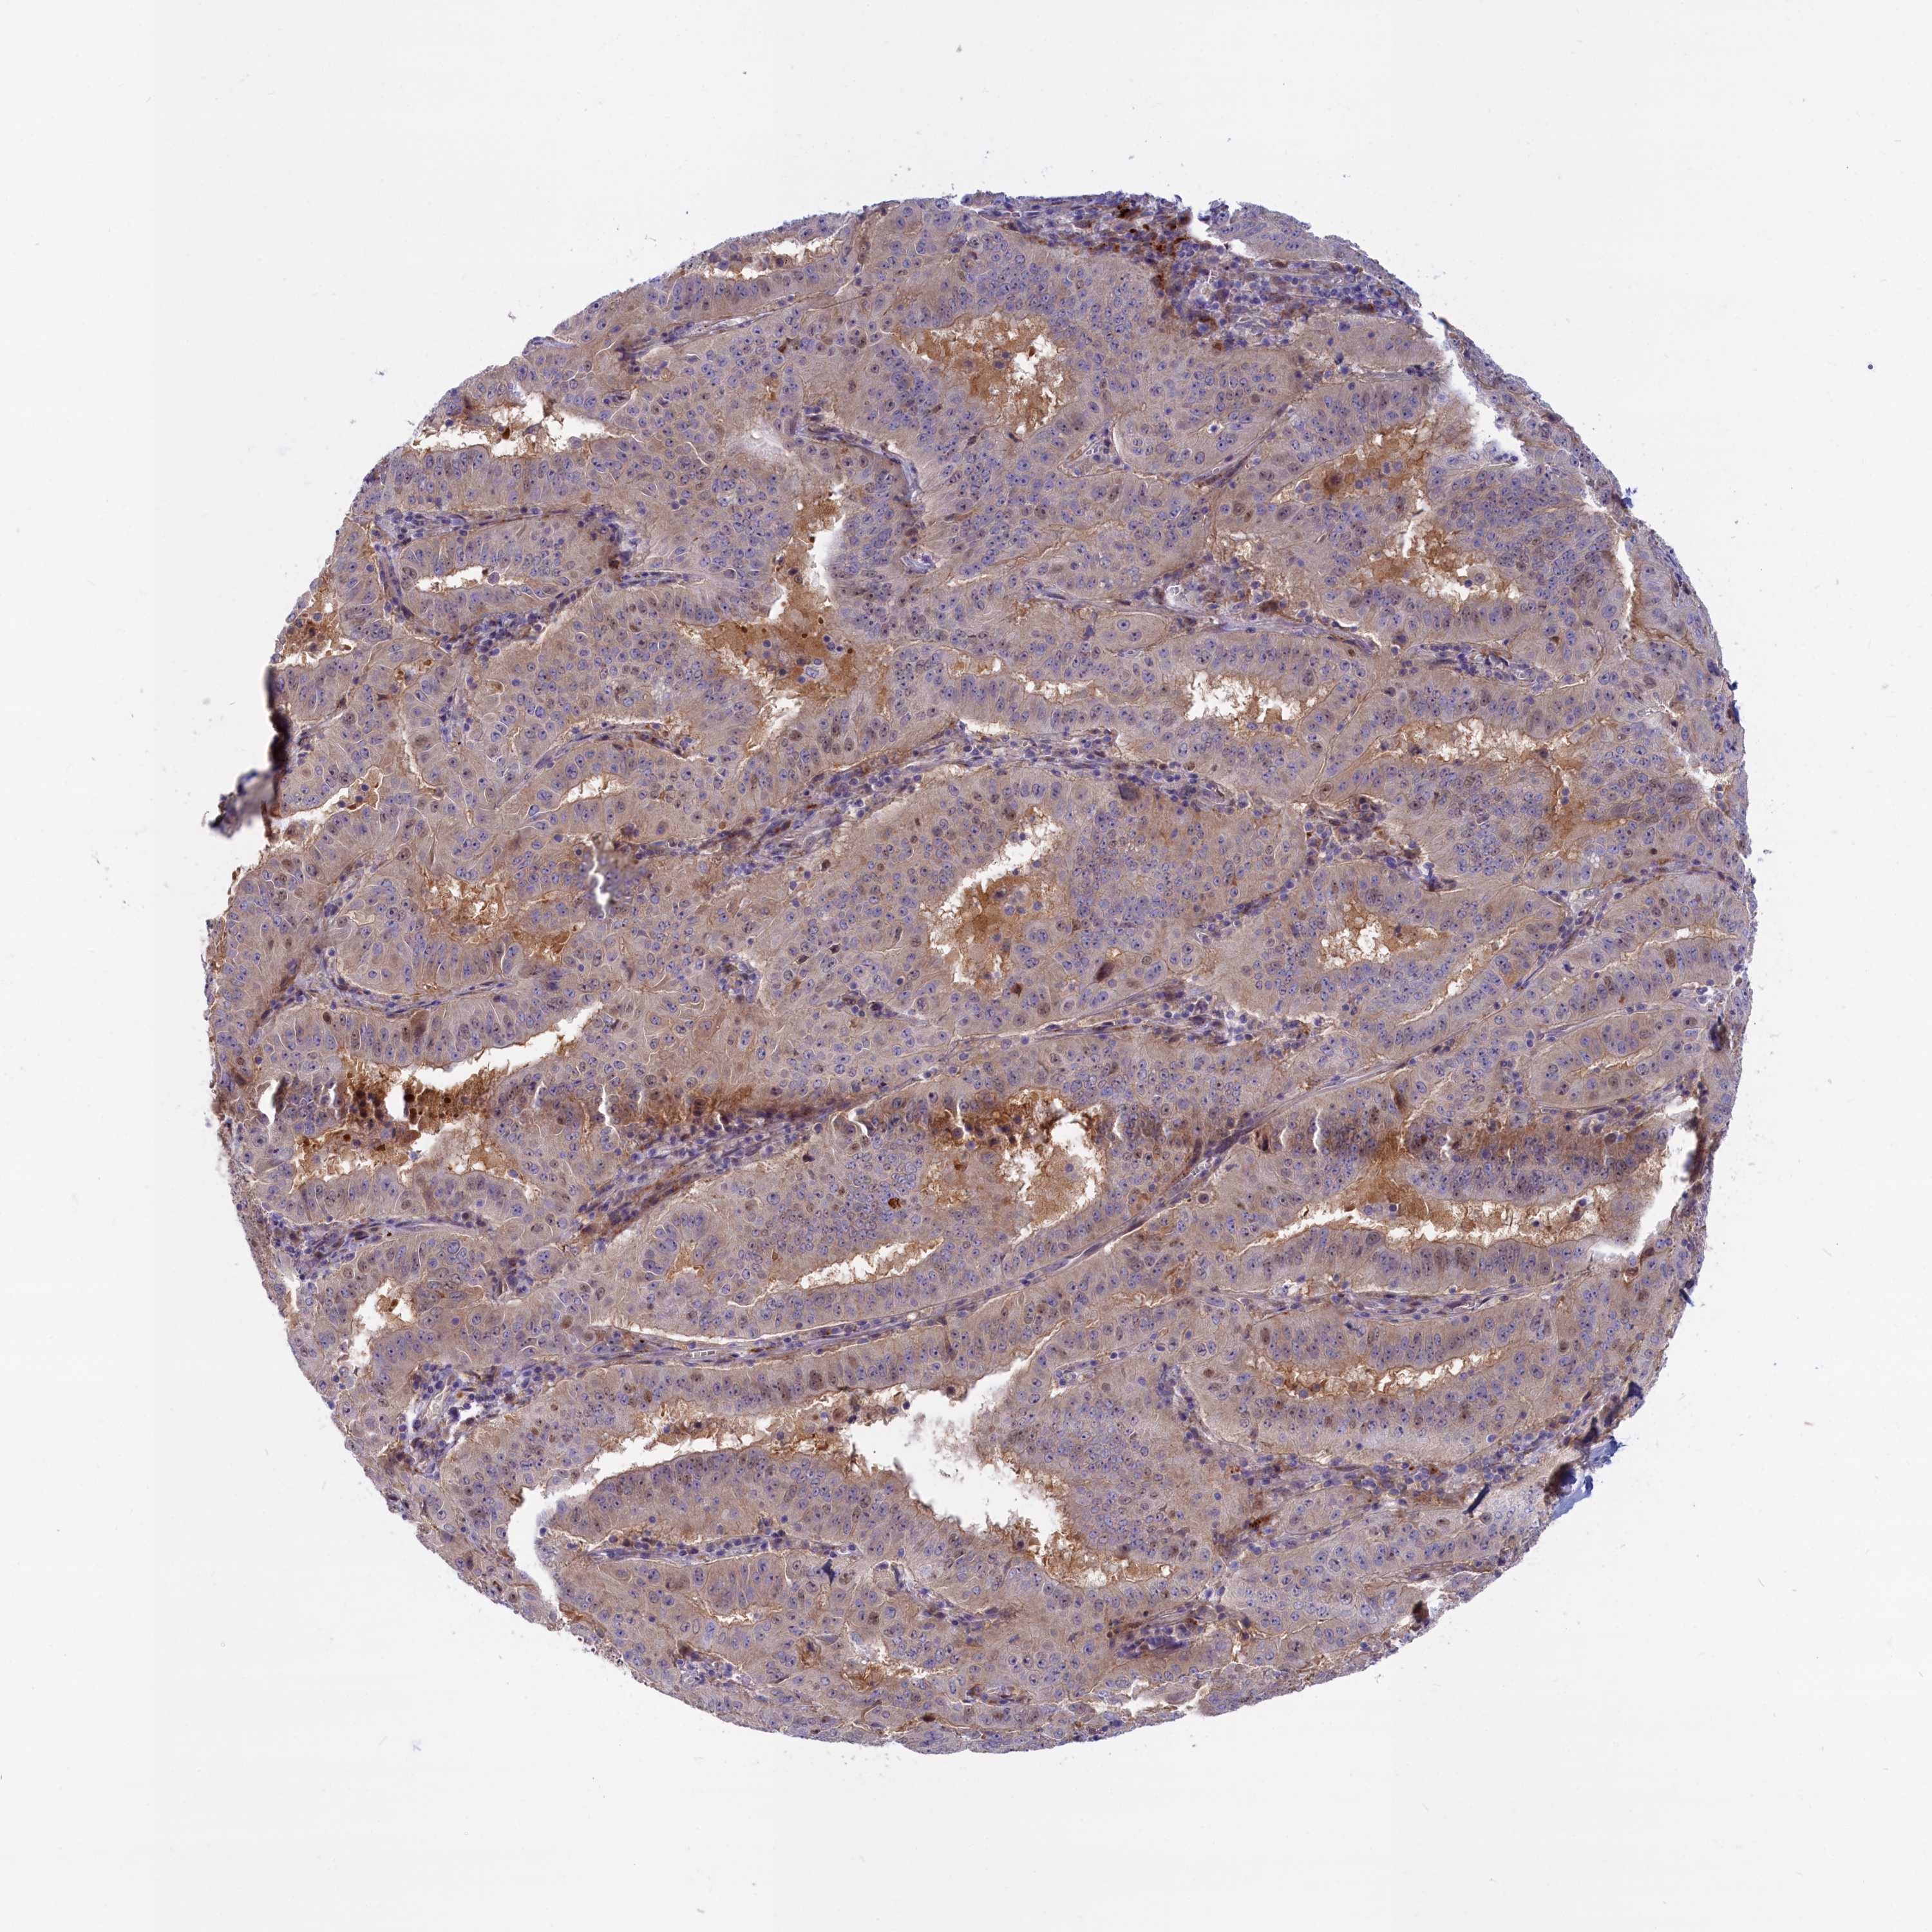

PANCREATIC CANCER - Protein expressioni

A mouse-over function shows sample information and annotation data. Click on an image to view it in a full screen mode. Samples can be filtered based on level of antibody staining by selecting one or several of the following categories: high, medium, low and not detected. The assay and annotation is described here.

Note that samples used for immunohistochemistry by the Human Protein Atlas do not correspond to samples in the TCGA dataset.

Antibody stainingi

Antibody staining in the annotated cell types in the current human tissue is reported as not detected, low, medium, or high, based on conventional immunohistochemistry profiling in selected tissues. This score is based on the combination of the staining intensity and fraction of stained cells.

Each image is clickable and will lead to virtual microscopy that enables deeper exploration of all samples and also displays staining intensity scores, fraction scores and subcellular localization as well as patient and tissue information for each sample.

Antibody HPA041971

Staining

High

Medium

Low

Not detected

Intensity

Strong

Moderate

Weak

Negative

Quantity

>75%

75%-25%

<25%

None

Location

Nuclear

Cytoplasmic/membranous

Cytoplasmic/membranous,nuclear

Adenocarcinoma, NOS